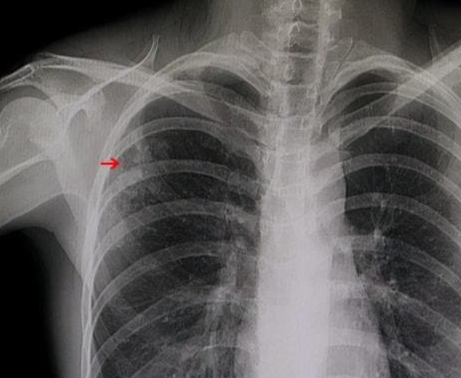

肺结节病不是疾病的判断,而是一个影像学的定义,主要是指影像学表现为直径≤3cm的局灶性类圆形密度增高的实性或牙齿性的肺部阴影,可以是孤立的,也可以是多发的,这些阴影被称为肺结节,而引起肺结节的原因是众多的,最引起人们关注的就是肺部的肿瘤。

如果要多发性的肺部结节>10个的弥漫性肺结节,大多是恶性肿瘤转移或者良性病变所致。也有一些肺的结节是孤立的,孤立性的结节就是单一的一个病灶,就要更加重视,这一个病灶也有可能是良性的,当然也可能是恶性的,良性的结节大多都是与炎症或者慢性炎症是相关的,而恶性结节就是肺部的肿瘤。